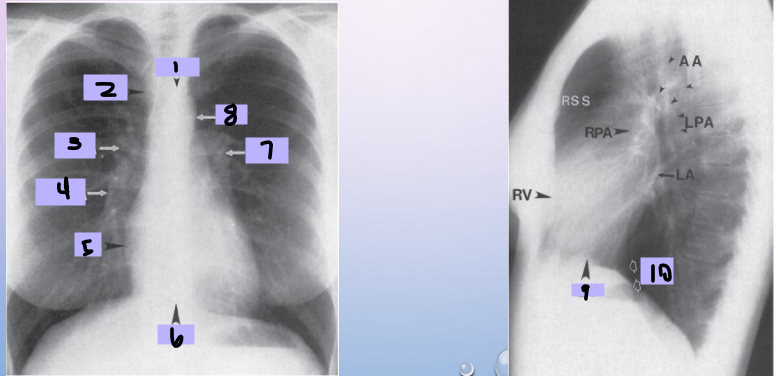

Aortic arch

#1

Superior vena cava

#2

Right pulmonary artery

#3

Right descending pulmonary artery

#4

Right atrium

#5

Right ventricle

#6

Left pulmonary artery

#7

Descending aorta

#8

Left ventricle

#9

Inferior vena cava

#10

Paratracheal stripe

#1

Aortic knob

#2

AP window

#3

Hila

#4